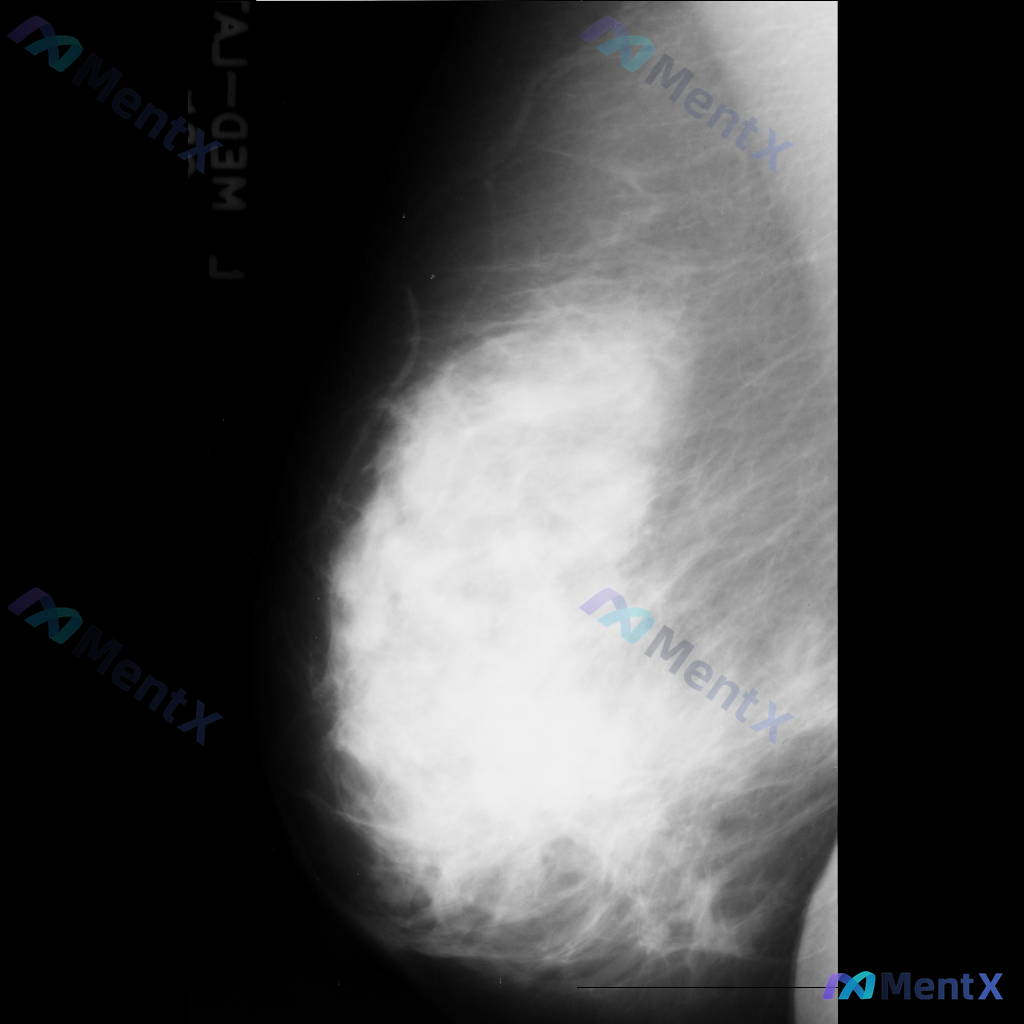

整理到一份乳腺钼靶影像资料,主要异常表现如下: - 部位:乳腺中部偏下方 - 影像征象:局灶性不规则腺体密度增高,伴结构扭曲 - 背景:致密型乳腺 目前仅单张影像资料,未提供其他体位、超声或临床病史。 想和大家讨论一下:单看这组异常表现,你会先往哪个方向考虑?后续如果要进一步明确,你觉得优先做什么检...

整理了一份乳腺影像的读片资料,想和大家讨论下判断方向: 基本影像信息 - 单侧乳腺X光片,投照体位考虑可能为内外斜位(MLO) - 乳腺组织构成:不均匀致密型 - 影像质量:曝光适中,清晰度良好,无明显伪影 - 可见结构:皮肤、皮下脂肪层、乳头乳晕、Cooper韧带显示尚可;未见明确钙化血管或腋窝淋...